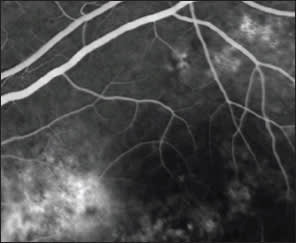

The two techniques for imaging vasculature are FA and ICG. A combination of phthalic acid with the plant resin resorcinol is used as the dye for FA, which fluoresces at a peak around 530 nm.6 Fluorescein leaks from damaged retinal vessels and can be used for evaluation of macular edema, venous occlusions and diabetic retinopathy. It delineates areas of choroidal nonperfusion in diabetic retinopathy and vascular leakage in choroidal neovascular membranes. ICG uses a tricarbocyanine dye that has a fluorescence peak around 800 nm. It is highly protein-bound and thus stays within choroidal vasculature better than fluorescein, which permits much-improved evaluation of the choroid. This advantage has made ICG the gold standard for diagnosis of the choroidopathies, including central serous retinopathy. ICG has milder side effects than FA for the most part; however, since it is iodine based, it is contraindicated in patients with iodine allergy or seafood allergy due to cross-reaction.7

3. Chronic CSR: FAF vs. FA

Most Optimal Technique

Advantages: Shows classic gutter appearance for CSCR; fully captures RPE disruption.

Limitations: Does not show active source of leakage or “hot spot”; does not show extent of SRF; uses blue light.

Alternative Technique

Advantages: Technique is appropriate for imaging both acute and chronic CSR.

Limitations: Invasive; adverse reaction to dye.